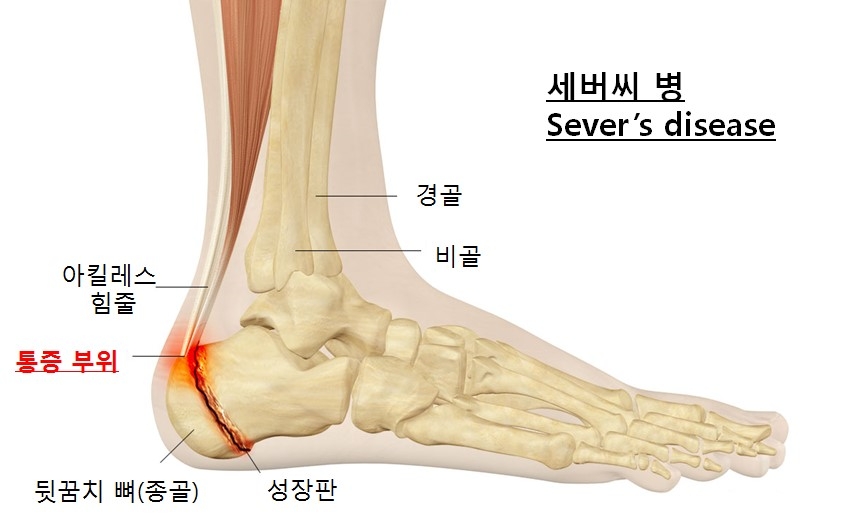

30일 의료계에 따르면 세버씨병이란 아킬레스힘줄이 뒤꿈치 뼈 골단을 잡아당겨 발생하는 질환 중 하나로 ‘뒷꿈치뼈 골연골증’이라고도 부른다.

그 원인은 보행 시 발생하는 반복적인 압력으로 인한 피로 골절이나 아킬레스건이 부착하는 부위에 아직 골화되지 않은 종골(뒤꿈치)의 성장판 때문이라 추정하지만 정확한 발생 원인은 밝혀지지 않았다. 주로 축구, 농구, 체조, 육상 선수들에서 많이 발생한다.

세버씨병의 경우 방사선 촬영을 통해 확인할 수 있다. 활동량이 많은 아이가 뒤꿈치 통증을 호소한다면 방사선 촬영으로 확인해 볼 수 있다. 방사선 촬영을 해보면 울퉁불퉁한 성장판이 관찰되기도 한다. 부드러운 형태보다 아킬레스 힘줄에 의해 당김이 발생할 때 불편함을 더 느낄 수 있다.